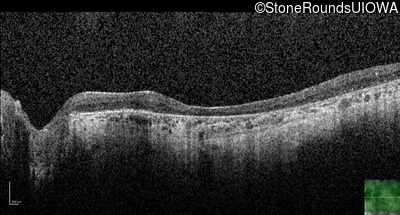

Optical Coherence Tomography - Right - 20/200 +2

Exemplar / OCT Stack